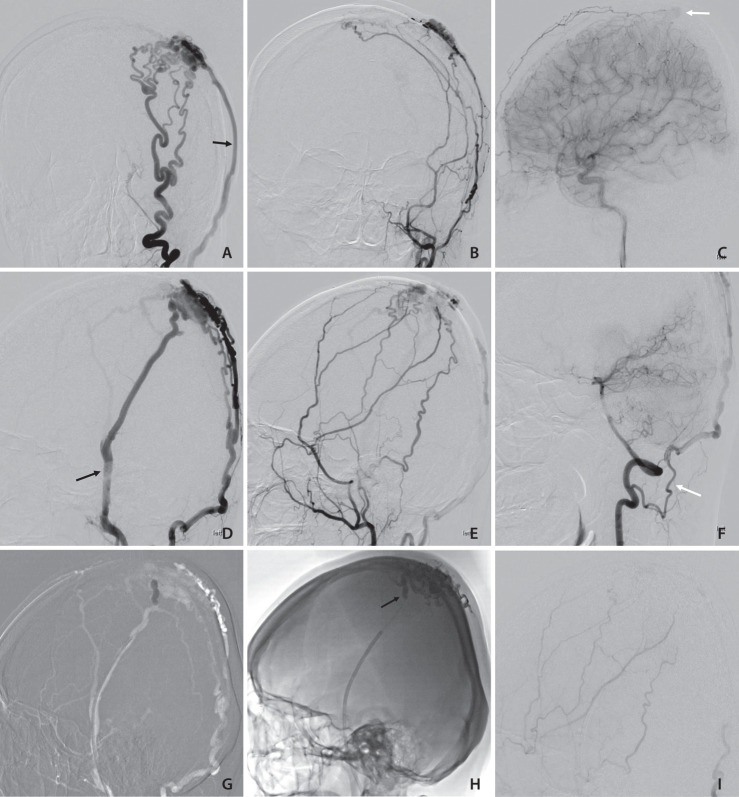

头皮动静脉瘘(AVF)是一种罕见的血管畸形,其特点是头皮动静脉系统连接异常。这些病变可导致严重的并发症,包括慢性头痛、耳鸣、外观畸形,严重者可导致高输出性心力衰竭或颅内出血。我们介绍了一例中年女性患者的病例,她的左顶叶头皮出现搏动性肿块已有 20 年病史。磁共振成像和脑血管造影证实存在头皮动静脉瘘,多条动脉从颈外动脉供血,静脉引流至左侧颈外静脉。由于供血动脉迂回曲折,经动脉方法无法成功,因此决定使用 Onyx-18 进行经静脉栓塞和球囊闭塞。手术后,动静脉瘘完全闭塞,没有出现并发症。该病例突出显示了经静脉栓塞加球囊闭塞作为复杂头皮动静脉瘘治疗方案的有效性,尤其是在经动脉入路具有挑战性的情况下。

Scalp arteriovenous fistulas (AVFs) are rare vascular anomalies characterized by abnormal connections between arterial and venous systems in the scalp. These lesions can lead to significant complications, including chronic headaches, tinnitus, cosmetic deformities, and in severe cases, high-output cardiac failure or intracranial hemorrhage. We present a case of a middle-aged female patient with a 20-year history of a pulsating mass on the left parietal scalp. Magnetic resonance imaging and cerebral angiography confirmed the presence of a scalp AVF with multiple arterial feeders from the external carotid artery and venous drainage into the left external jugular vein. Due to the tortuosity of the feeding arteries, a transarterial approach was unsuccessful, leading to the decision to perform transvenous embolization with balloon occlusion using Onyx-18. The procedure resulted in complete obliteration of the AVF without complications. This case highlights the efficacy of transvenous embolization with balloon occlusion as a treatment option for complex scalp AVFs, particularly when transarterial access is challenging.